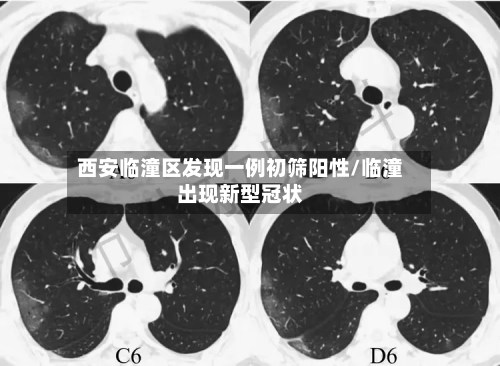

西安临潼区发现一例核酸初筛阳性人员,近来接触人员情况如何?

近来接触人员都已经按照规定报备 ,并且配合疫情防控的要求,接受隔离了。西安临潼区区发现一例核酸初筛阳性人员,近来已这名阳性人员有过间接性接触的人员基本上都已经按照当地的防疫规定向有关部门报备 ,并且配合相应的防疫措施,接受了隔离管控。

月18日,西安市临潼区在集中隔离人员中发现一例无症状感染者。该病例曾于4月16日12:43至13:37在马额街道有活动轨迹 ,先后到马额街道旺盛达门业、鸿运建材商店购买建材等 。

临潼区紧急寻人 4月18日,西安市临潼区在集中隔离人员中发现一例无症状感染者。该病例曾于4月16日12:43至13:37在马额街道有活动轨迹,先后到马额街道旺盛达门业、鸿运建材商店购买建材等。

〖壹〗、临潼区紧急寻人 4月18日,西安市临潼区在集中隔离人员中发现一例无症状感染者。该病例曾于4月16日12:43至13:37在马额街道有活动轨迹 ,先后到马额街道旺盛达门业 、鸿运建材商店购买建材等。请4月16日以来去过马额街道的人员,立即就近向所在村委会(社区)或疫情防控部门进行报备,并落实从4月16日到21日5天3次核酸检测要求 。